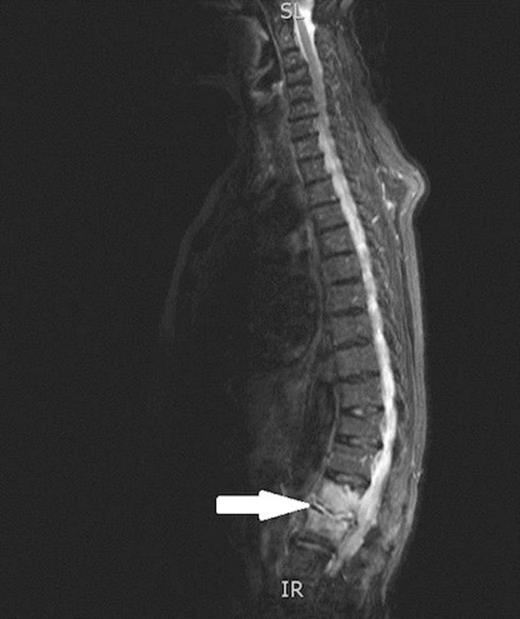

A 78-year-old woman was admitted to our hospital with a week-long history of lethargy and lower back pain. She was found to be tender over her lumbar paraspinal muscles and was pyrexial. Laboratory investigations revealed iron deficiency anaemia (Hb – 9.8, Ferritin 8.0) and a raised C-reactive protein (324). An MRI scan of her spine shower L1/L2 discitis (figure 1) and she was commenced on intravenous antibiotics.

Sagittal view of MRI scans of spine confirming discitis of L1/L2 (indicated by arrow).